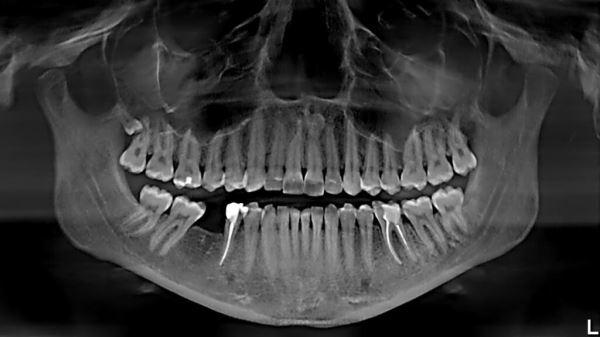

Часто после лечения зубов у пациента проходят кожные заболевания, к примеру, экземы. Источник изображения: orthodonticproductsonline.com